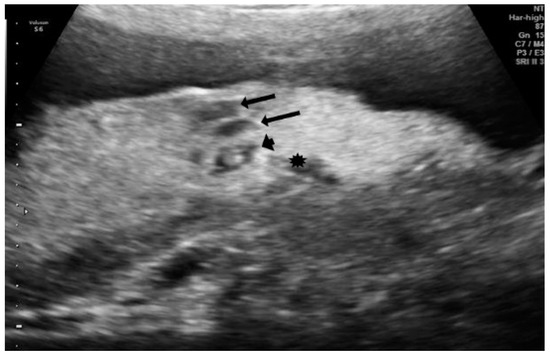

| 1 | Lakes > 30% |

| 1 | Subchorionic edema |

| Lakes > 30% | 7 (70%) | 6 (20%) |

| Subchorionic edema | 6 (60%) | 2 (7%) |